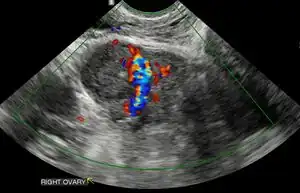

Obstetric ultrasonography may also be used to detect and diagnose pregnancy. It is very common to have a positive at home urine pregnancy test before an ultrasound. Both abdominal and vaginal ultrasound may be used, but vaginal ultrasound allows for earlier visualization of the pregnancy. With obstetric ultrasonography the gestational sac (intrauterine fluid collection) can be visualized at 4.5 to 5 weeks gestation, the yolk sac at 5 to 6 weeks gestation, and fetal pole at 5.5 to 6 weeks gestation. Ultrasound is used to diagnose multiple gestation.[3][19]

Ultrasound: early pregnancy -

Ultrasound: failed early pregnancy

Ultrasound is also a common tool for determining viability and location of a pregnancy. Serial ultrasound may be used to identify non-viable pregnancies, as pregnancies that do not grow in size or develop expected structural findings on repeated ultrasounds over a 1-2 week interval may be identified as abnormal.[34] Occasionally, a single ultrasound may be used to identify a pregnancy as non-viable; for example, an embryo that is greater than a certain size but that lacks a visible heart beat may be confidently determined to be not viable without the need for follow up ultrasound for confirmation.[34]